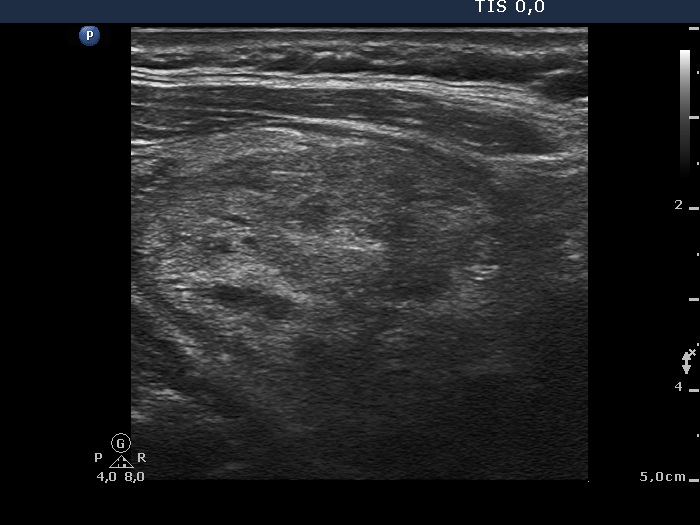

Ultrasonography: A large lesion composed of multiple moderately hypoechogenic and hyperechogenic nodules occupied almost the entire right lobe. There was a small hypoechogenic nodule in the upper pole while a cystic nodule in the central part of the left lobe. The former presented coarse and microcalcifications, too. The vascularization was not specific.